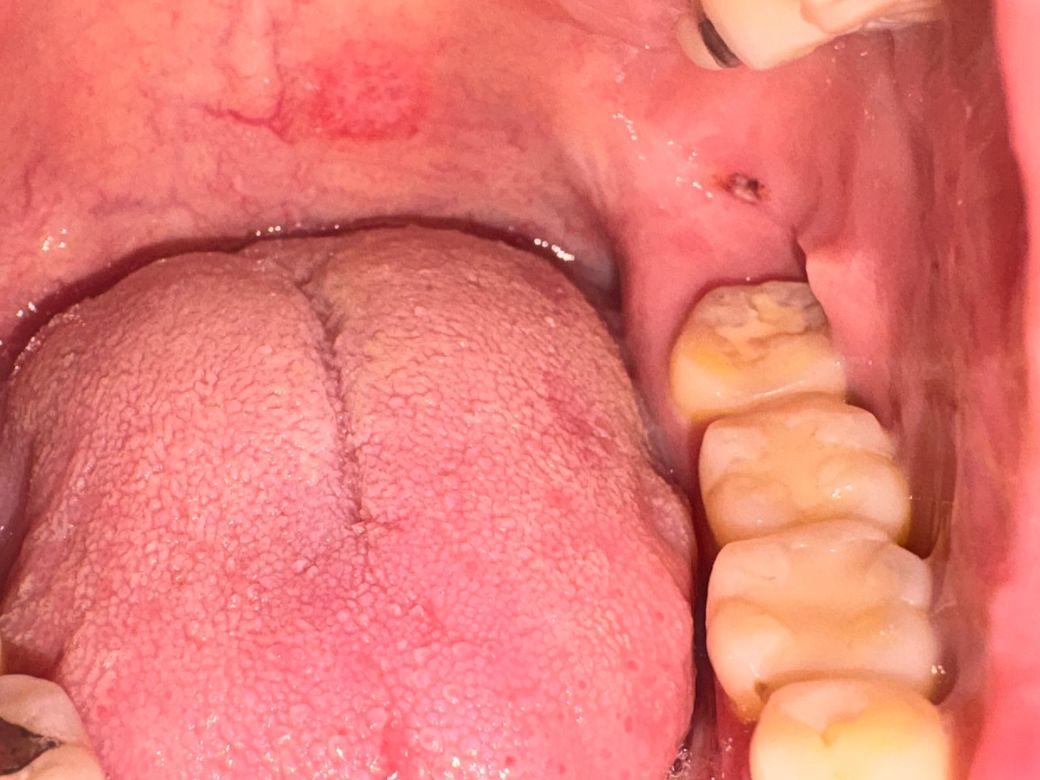

그런데 오늘 입안을 보는데 사랑니쪽에 검은색으로 보이는데 혹시 이게 뭘까요? 갑자기 생겼습니다

만졌을 때 아주 살짝 튀어나와있고 말랑합니다

구내염처럼 하얗지도 않고 통증도 없습니다

피가 고인것처럼 검은색이라 뭘까 싶습니다

• 설명만 보면 전형적인 구내염보다는 점막하 출혈(혈종) 가능성이 더 높습니다.

구내염은 보통 중앙이 하얗거나 노란 막처럼 보이고 통증이 뚜렷한 경우가 많습니다. 반면 말씀하신 병변은 검은색, 무통, 약간 말랑한 촉감이라는 점에서 작은 혈관이 터지면서 점막 아래에 피가 고인 형태와 더 일치합니다. 씹힘, 음식 자극, 무의식적인 외상으로도 흔히 발생합니다.

임상적으로는 대부분 1주에서 2주 사이 자연 소실됩니다. 특별한 처치는 필요 없고 자극만 피하면 됩니다.

다만 크기가 커지거나, 2주 이상 지속되거나, 반복적으로 같은 위치에 생기면 색소성 병변이나 혈관성 병변 감별이 필요하므로 치과 또는 구강외과 진료가 권장됩니다.

피가 고인것 맞는 것 같습니다. 상처도 생긴것 봐서는 치아에 씹히거나 칫솔에 상처가 난것 아닐까 싶습니다. 1주일 정도 자극을 주지 말고 지켜보심 없어질겁니다.